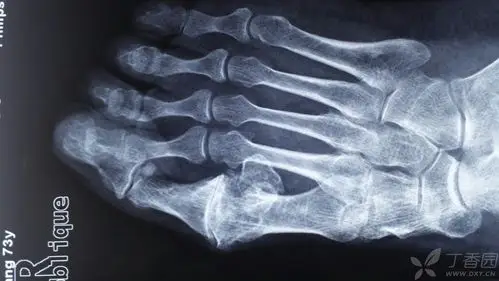

糖尿病人脚上的伤口流脓为什么一直在加重?怎么才能治好?

伤口造口护理在糖尿病足的成功应用(副本)